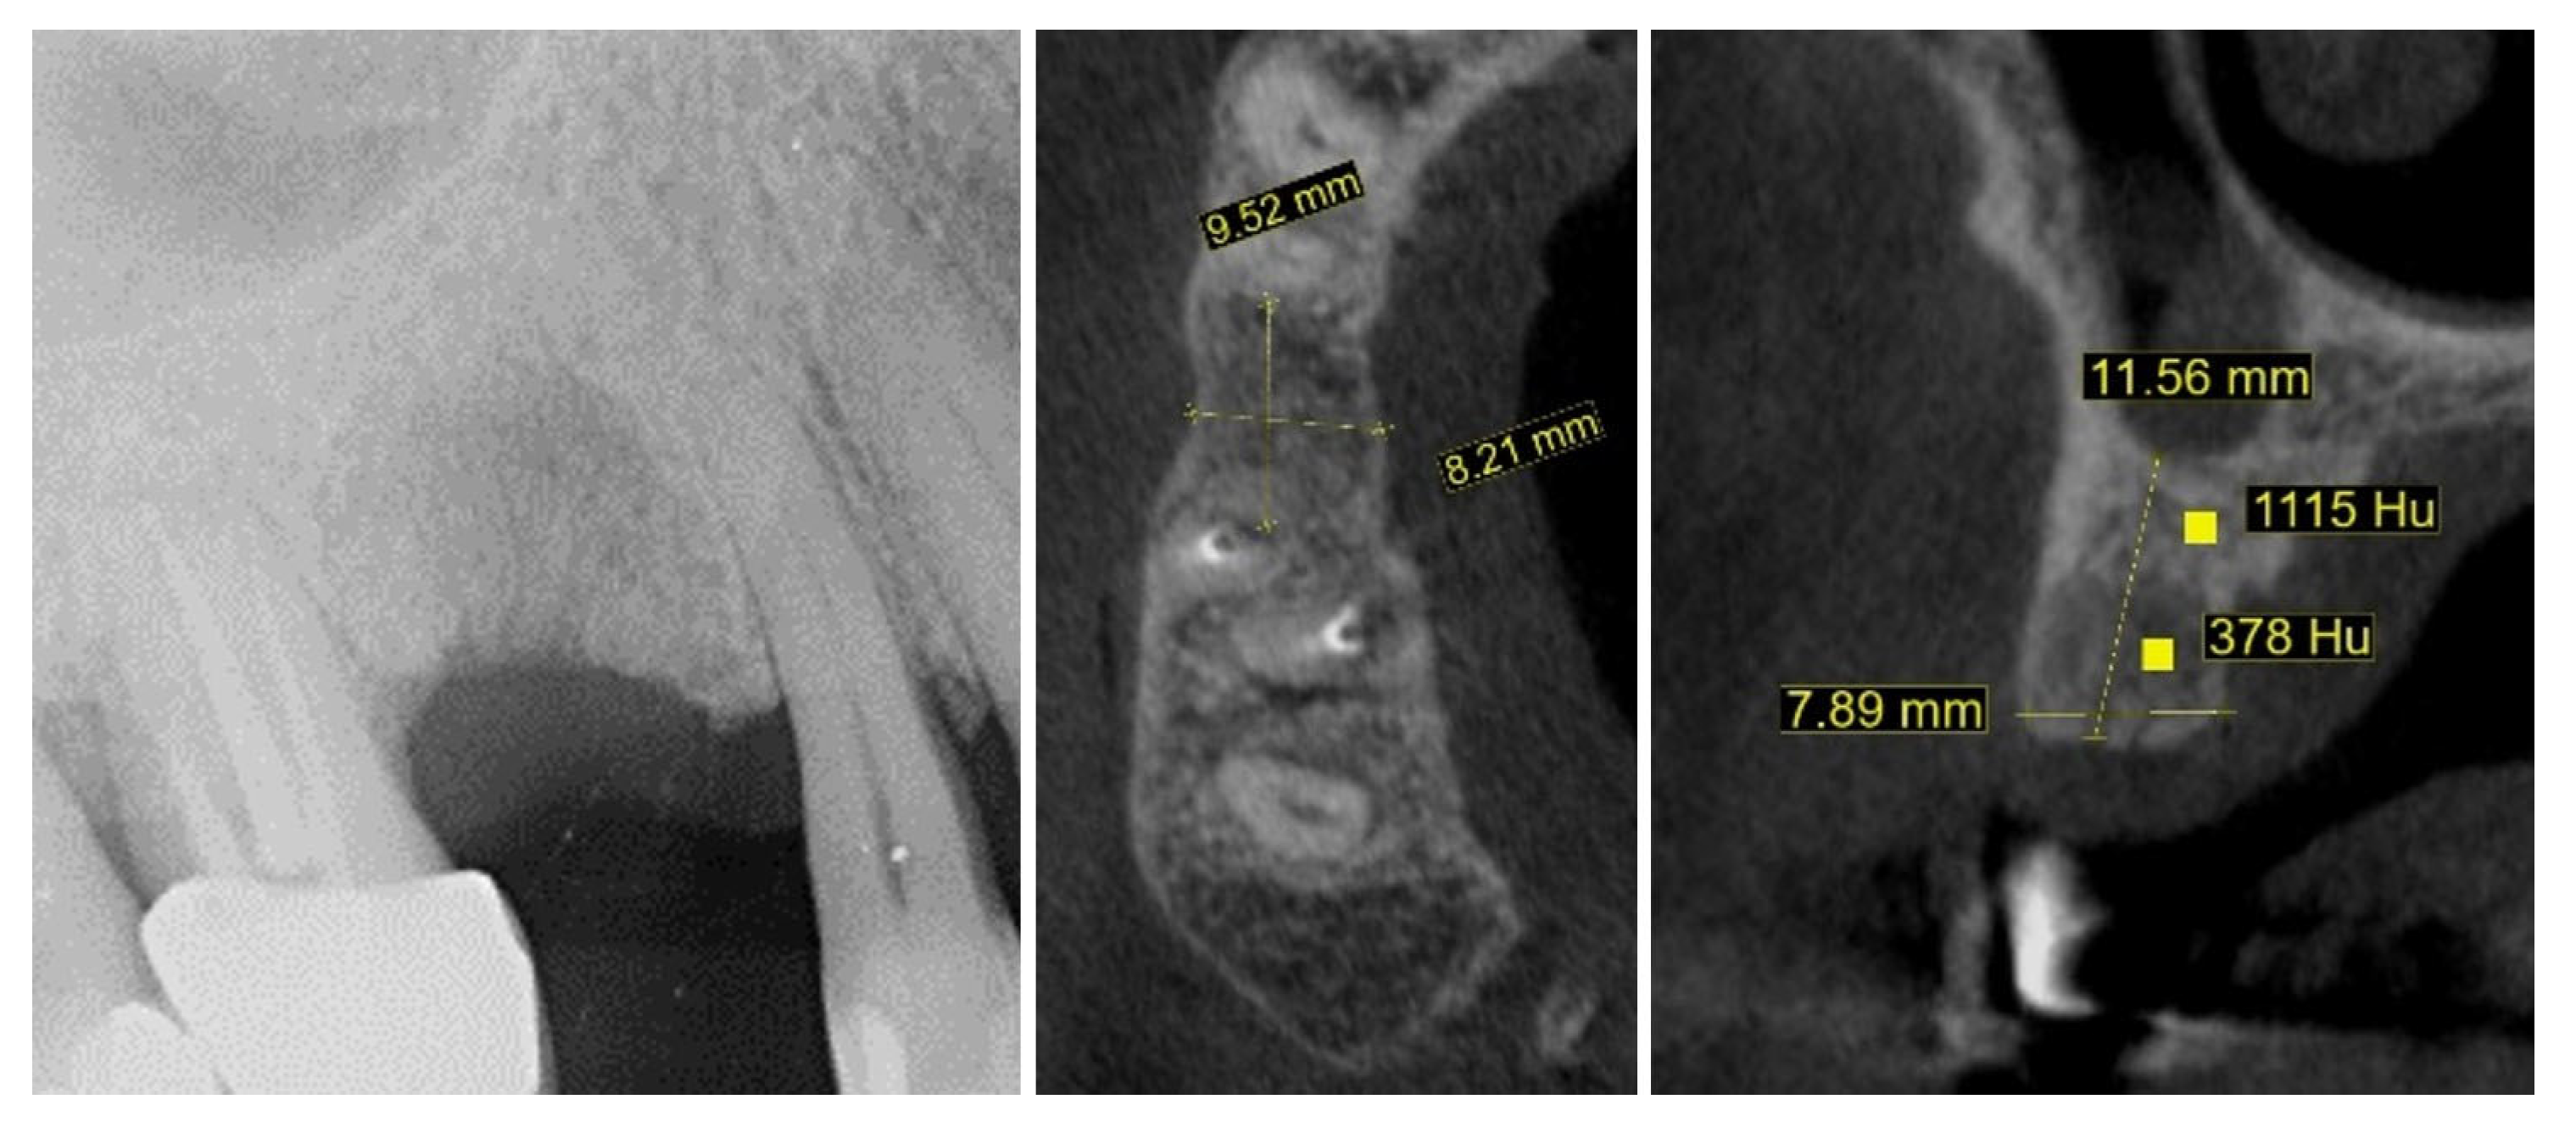

New cone-beam computed tomography (CBCT), performed to assess the morphology of the healed ridge, demonstrated a complete healed crestal bone with a bucco-lingual width of 8.2 mm. In the sagittal plane, the total vertical bone height measured 11.5 mm, suggesting adequate dimensions for implant placement without additional bone augmentation. The bone density measurement presented a high BMD value in the apical part of the crest while the density in the newly formed bone was relatively low (Figure 4).

Figure 4.

One year after autogenous healing of the extraction site.